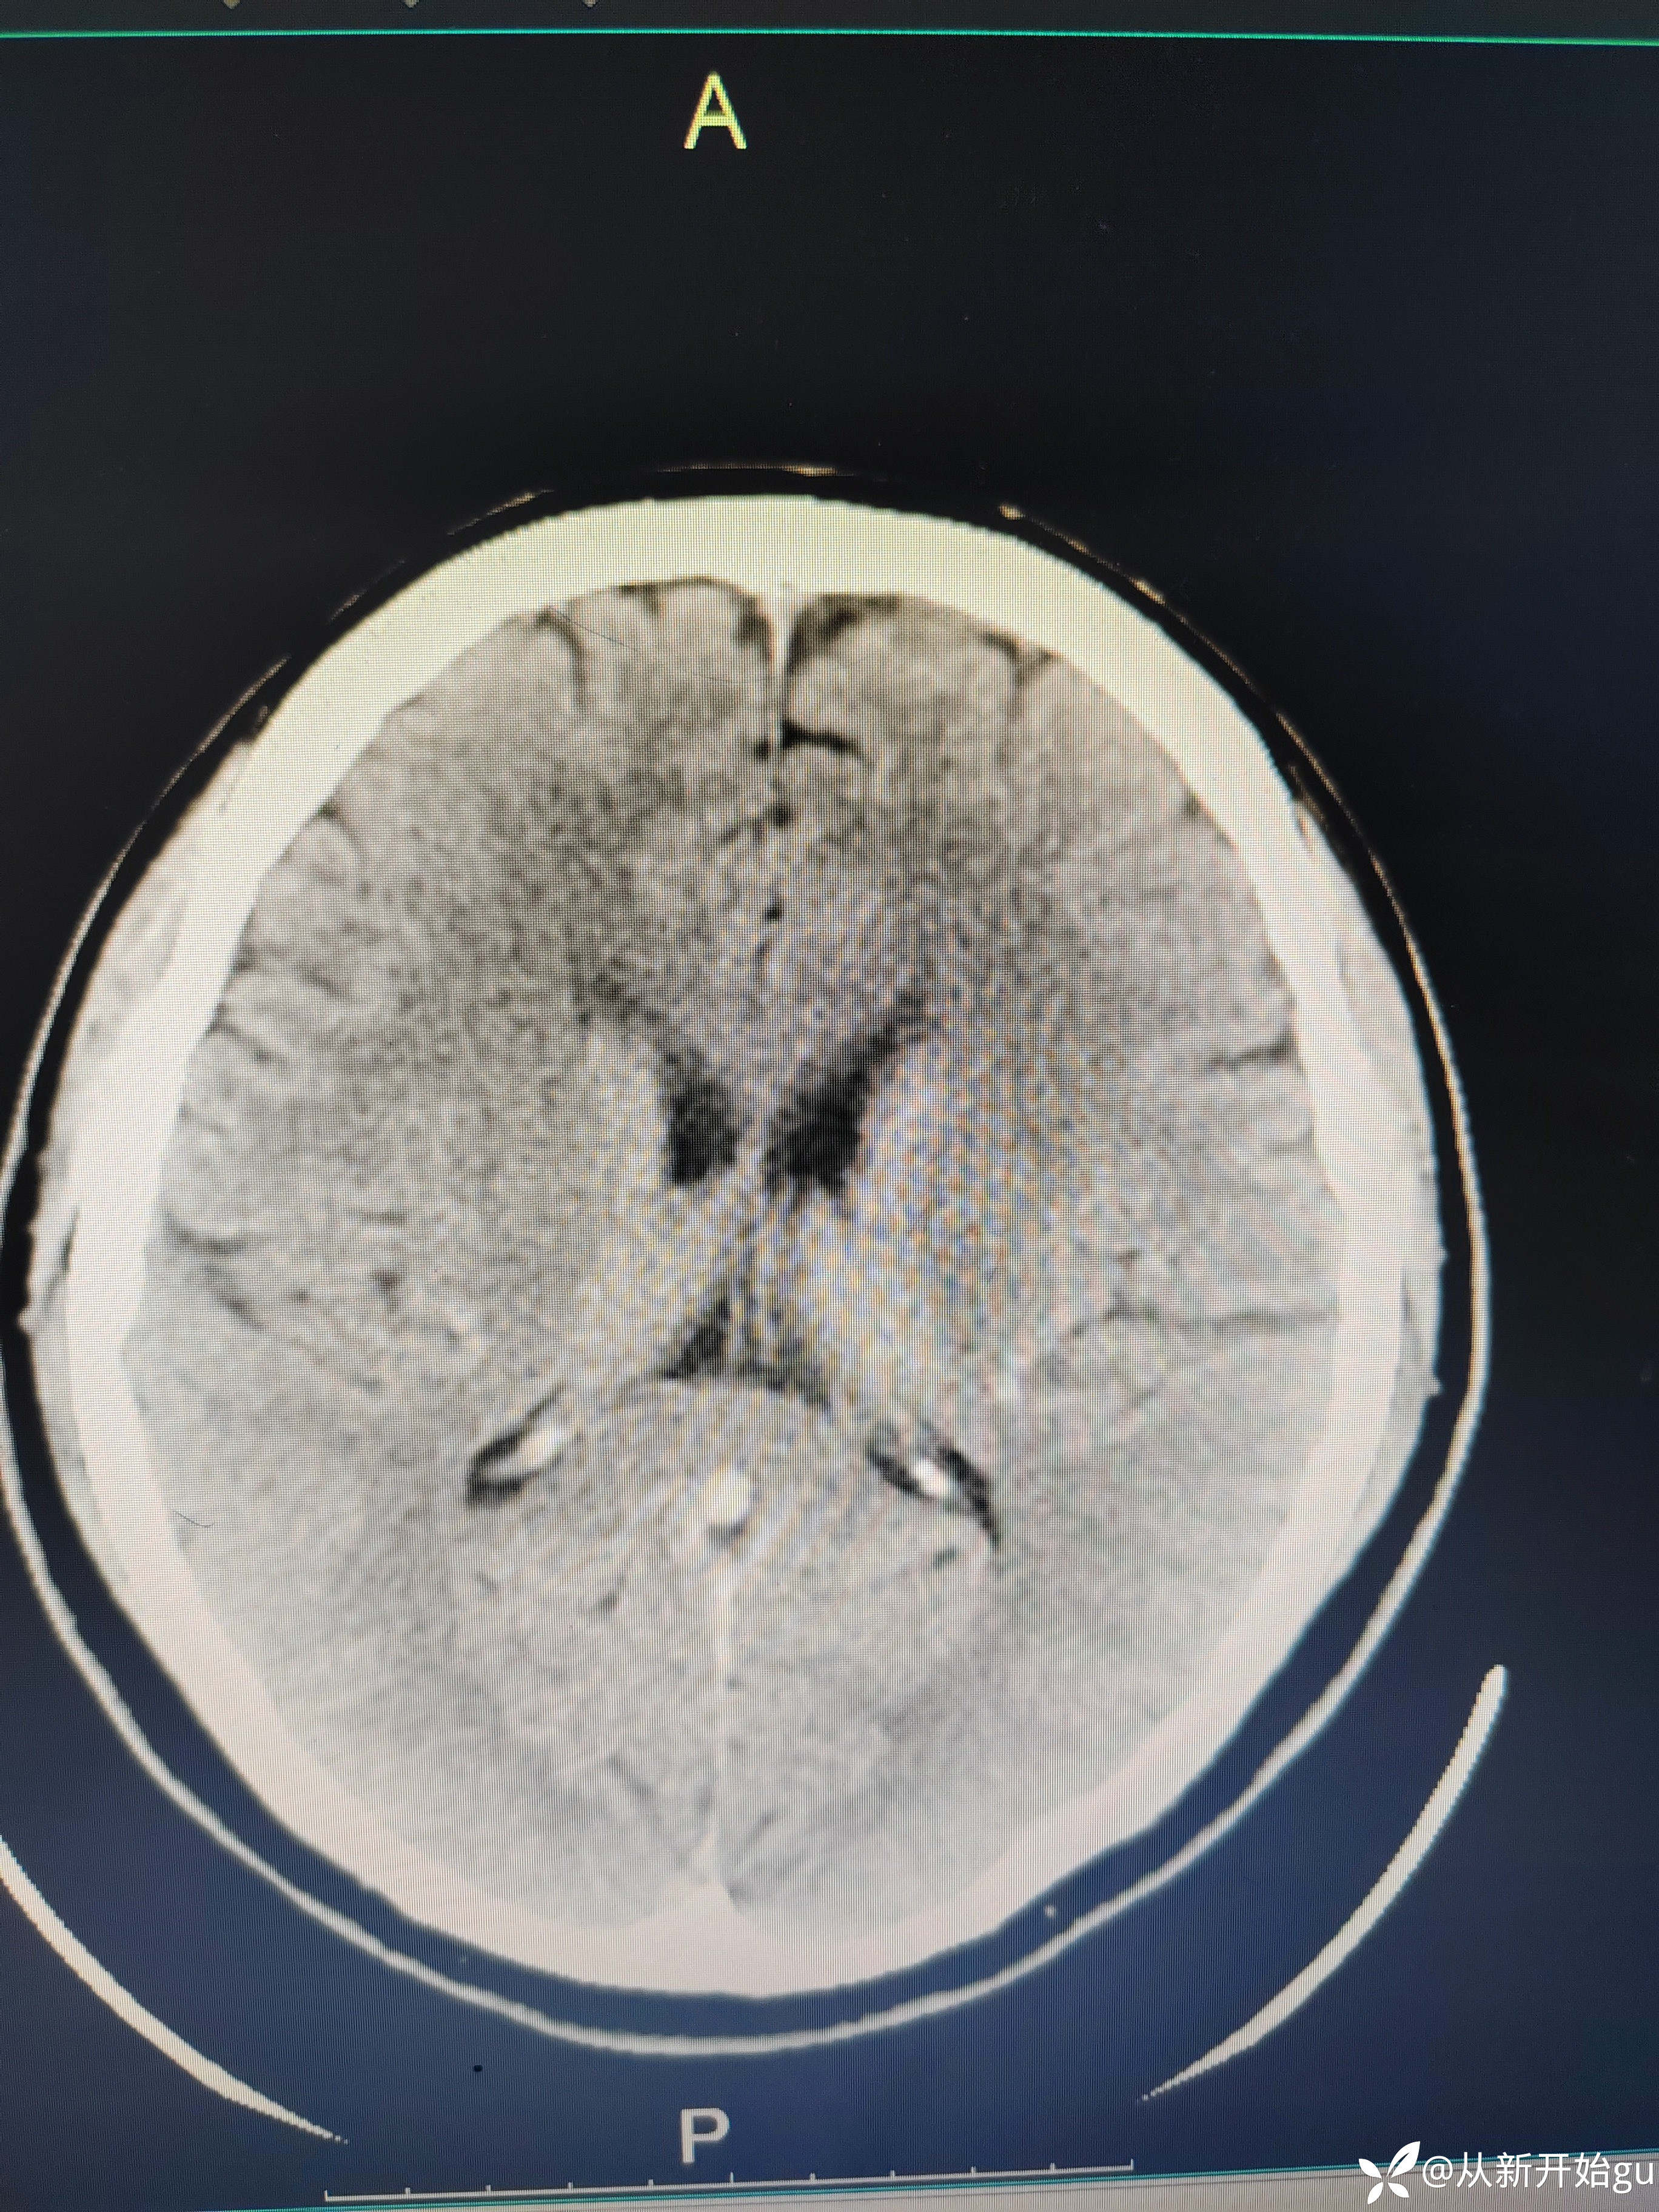

患者51岁男性,主因左下肢活动障碍1小时来院。既往高血压病史,查体,右侧鼻唇沟稍浅(家属诉之前就这样),神舌居中,左侧下肢肌力5级-,左侧跟膝胫试验欠稳准,左侧巴氏征阳性,评分也就一分,鼻唇沟稍浅未纳入。行颅脑CT检查如图所示